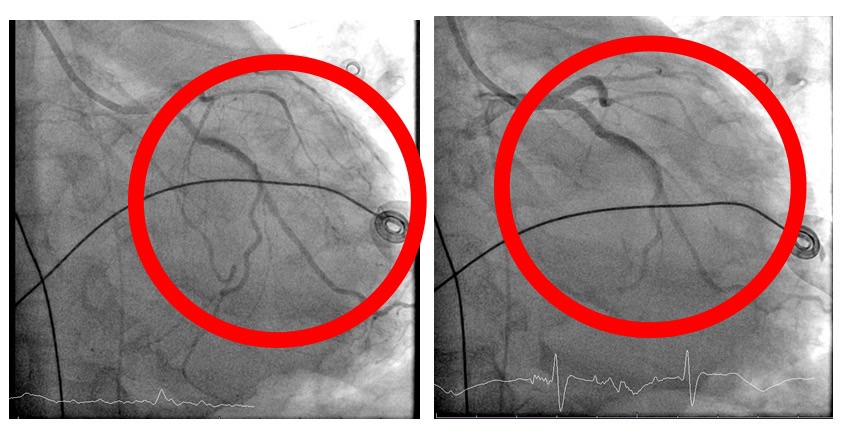

在葉克膜支持下,心臟內科張偉俊醫師立即安排緊急心導管檢查,歷時7小時完成高難度冠狀動脈鈣化旋磨與震波氣球治療(Rota-Shock策略),成功打通三條嚴重阻塞之冠狀動脈並完成支架置放,同步放置主動脈內氣球幫浦(IABP),以提升心臟輸出量、減輕心臟負荷並穩定血流動力。